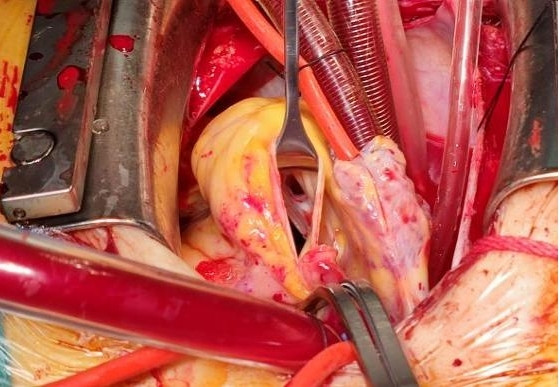

1 资料与方法患者女性,19岁,因“突发胸痛14 h”入院。患者14 h前无明显诱因出现胸骨后疼痛,呈紧缩感,伴有胸闷、呼吸困难,间断咳嗽。近期有听力下降、腹泻病史。8 h前就诊于外院时查体:体温测不出,Bp 53/36 mmHg(1 mmHg=0.133 kPa),呼吸40次/min, 脉搏137次/min,SPO2 93%,神志淡漠,全身皮肤湿冷,黏膜无黄染及出血点,颈静脉无怒张。听诊双肺呼吸音粗,可闻及满肺湿啰音,心音不清,腹部查体无异常,双下肢足背动脉搏动对称。化验结果提示WBC 29.3×109/L,NE 85.4%,TnT 93 ng/L,pro-BNP 2 047 pg/mL,PCT 0.11 ng/mL, 血气分析:pH 7.349,PCO2 31.2mmHg,PO2 67.2 mmHg,HCO3- 17.2 mmol/L,Lac 5.7 mmol/L。心电图提示:窦性心动过速、AVR导联ST段抬高,余导联ST段压低;床旁心脏超声提示EF 52%,二尖瓣中度返流、三尖瓣中重度返流,未见室壁节段性运动性异常。考虑心源性休克,原因尚不明确,给予机械通气、血管活性药物、补液等抗休克治疗,同时联系本院急诊ECMO团队,本院急诊ECMO团队到达现场后,患者突然出现室颤,给予胸外按压及电除颤后逐渐恢复窦律,立即进行V-A ECMO上机指征及预后评分SAVE评分评估,符合V-A ECMO上机适应证,约30 min成功上机运转,流量3.5 L/min,复查外周动脉血气分析: pH 7.305,PCO2 21 mmHg,PO2 73.4 mmHg,HCO3- 10.5 mmol/L,Lac 8.4 mmol/L。后转运至本院急诊病房,转运途中行生命体征、血气分析、ACT等常规监测,至病房后患者ECMO支持下血压仍需大剂量血管活性药物维持且脉压差较小,观察ECMO动静脉管路颜色极为接近,床旁经胸心脏超声提示主动脉瓣重度返流,为明确原因立即行急诊CT检查及床旁经食道超声心动图检查。本院肺CT(图 1)提示肺水肿,床旁经胸心脏超声提示主动脉瓣大量返流但心室收缩可,请超声影像科进一步行床旁经食道超声检查提示无冠窦呈瘤样凸向右房侧,瘤壁上可见宽约0.6 cm破口;主动脉瓣舒张期无冠瓣脱向左室流出道侧(图 2、图 3)。立即请心血管外科会诊,急诊行主动脉瓣机械瓣膜置换术+主动脉窦修补术+房间隔造口术+主动脉球囊反搏置入术+心脏起搏器置入术,术中探查与经食道超声所见相符(图 4、图 5),考虑左心功能差,左心压力较高,行房间隔造口术。术后复查胸片肺水肿基本消失(图 6),继续呼吸机与ECMO支持,因患者肺功能良好,自主呼吸良好,为减少呼吸机相关肺损伤、呼吸机相关肺炎等发生,术后第4天神志清醒后拔除气管插管,机械通气减轻左心前后负荷的作用去除后,继续ECMO与IABP支持,ECMO增加左心后负荷时IABP可降低左室后负荷,达到左心减压的目的,术后第10天心功能恢复,下调ECMO流量后循环可维持,予以撤离ECMO,术后第12天撤离IABP,后停用肝素持续泵入抗凝,达肝素皮下注射联用华法林口服抗凝3 d后,单用华法林口服抗凝,维持INR达标,在康复期间患者活动时左下肢疼痛,左侧足背动脉搏动减弱,下肢动静脉超声提示左侧股浅动脉血栓形成,期间增加华法林剂量后血栓未见明显变化,后行下肢股浅动脉切开取栓术,术后33 d患者完全康复顺利出院。

| 图 4 术中所见 |

主动脉窦瘤较小或未破裂时患者可能完全没有症状,破裂后根据破口大小、破入部位的不同会产生不同的血流动力学变化,产生相应的临床表现也会不同。当破入右心时,主动脉与右心之间的压力差增大,引起右心容量负荷增加,严重者可出现肺动脉高压;与此同时,因大量左向右分流导致体循环血流量明显减少,易进展为急性心源性休克[6-8]。本案例患者术中探查考虑为先天性无冠窦瘤,既往窦瘤未破裂时无明显症状,破裂后患者突发胸痛、胸闷、呼吸困难,很快出现心源性休克,且V-A ECMO支持下患者血压仍需大剂量血管活性药物维持且脉压差较小,与窦瘤破入右房后体循环血流量明显减少出现的血流动力学改变相符,右心容量负荷增加导致的肺水肿与肺CT表现一致。